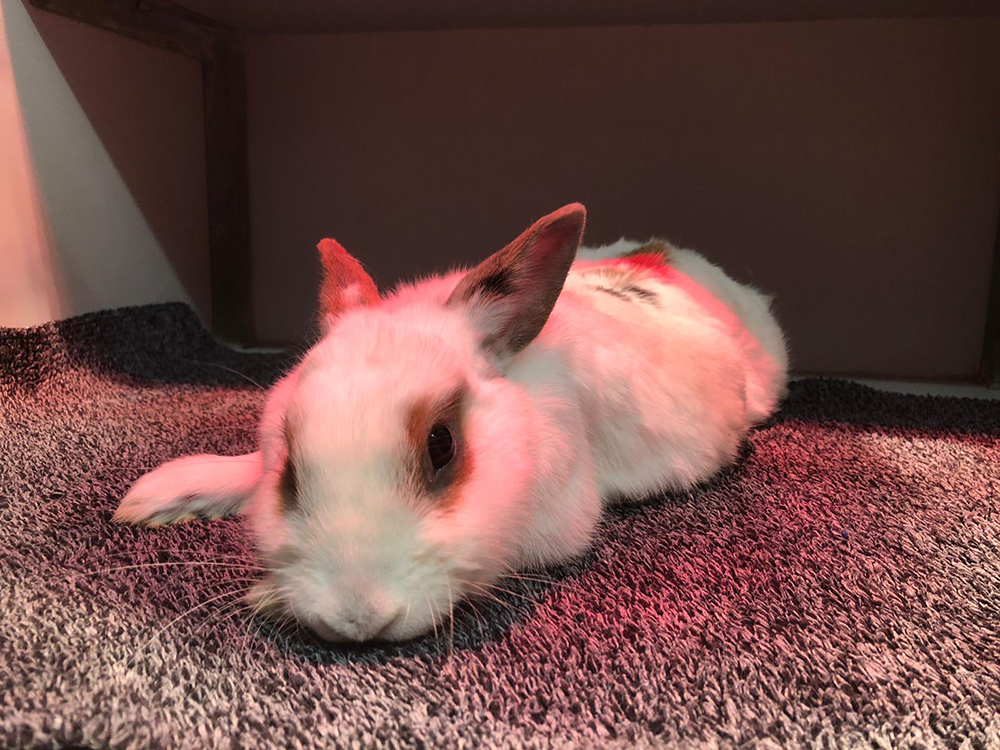

Wanneer de operatie klaar is, krijgt ze een injectie om sneller wakker te worden. Totdat ze reageert krijgt ze nog zuurstof toegediend. Omdat dieren onder narcose snel afkoelen, wordt ze vervolgens in de couveuse gelegd. Zowel onderkoeling als oververhitting kunnen gevaarlijk zijn. Om die reden houden we de temperatuur goed in de gaten en handelen naar bevinden met behulp van kruiken, warmtelamp en/of airco. Voordat de voedster naar huis mag, zorgen we altijd dat er nog wat voer ingegeven wordt. Hiermee zorgen we voor een betere uitgangssituatie voor het herstel.

Hieronder de sterilisatie van het konijn in beeld